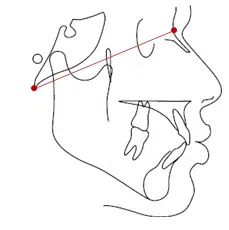

Ba-N Plane

این پلن از اتصال دو نقطه ی Basion و Nasion تشکیل شده است. از این پلن برای نشان دادن کرانیال بیس استفاده می شود و در این زمینه نسبت به پلن SN و Bolton دقیق تر است.

از این پلن در آنالیزهای Ricketts و McNamara به عنوان پلن مرجع استفاده شده است.